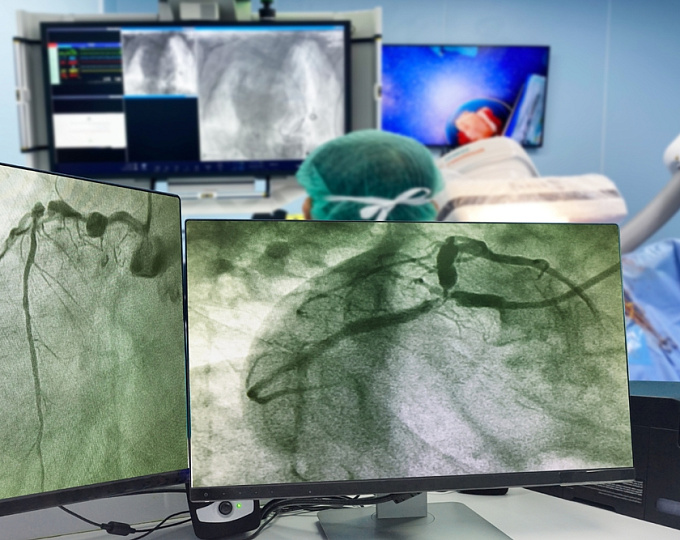

Катетерная аблация фибрилляции предсердий при амилоидозе сердца

Катетерная аблация является одним из наиболее эффективных методов контроля синусового ритма у пациентов с фибрилляцией предсердий (ФП).

Несмотря на высокую частоту встречаемости ФП у пациентов с амилоидозом сердца, эффективность и безопасность катетерной аблации у таких больных остается неопределенной.